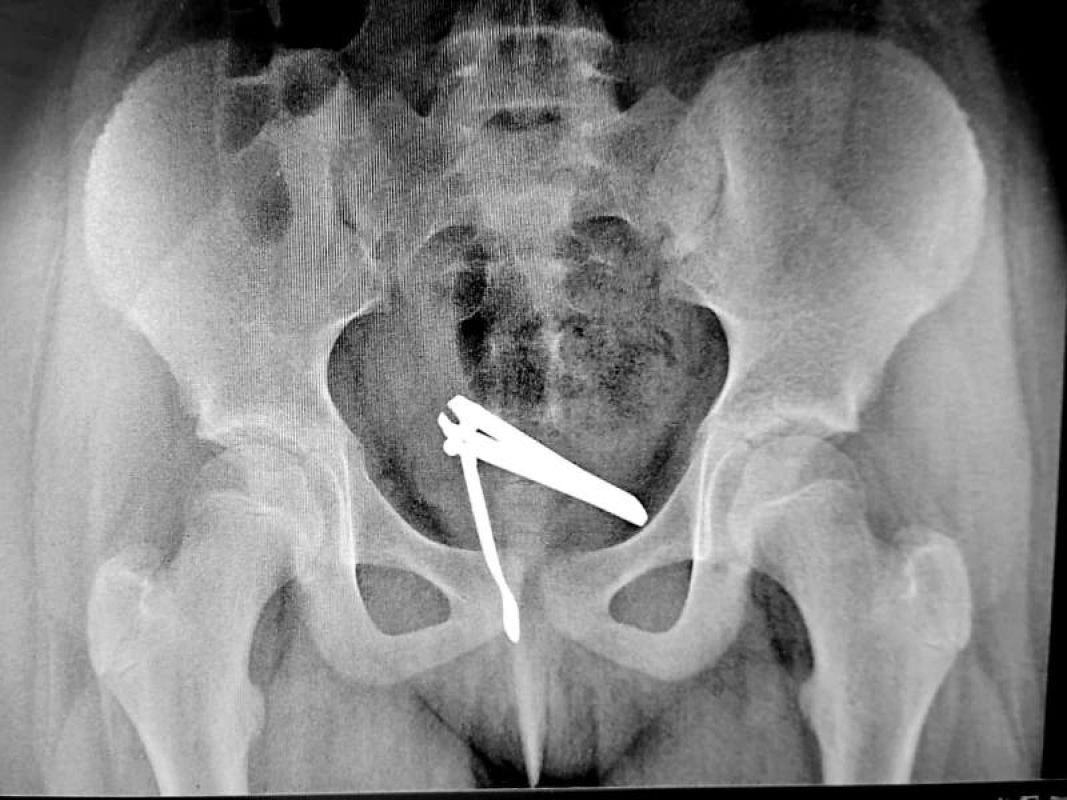

В Липецке в больницу попала маленькая девочка с кусачками в интимном месте. Об этом сообщил телеграм-канал «Липецк с огоньком».

По данным источника, в центре истории оказалась 5-летняя липчанка, которая познавала мир. Попытка завершилась неудачей, и щипцы попали вовсе не туда, куда нужно.

На помощь девочке пришли врачи областной больницы. Кусачки пришлось извлекать хирургам.